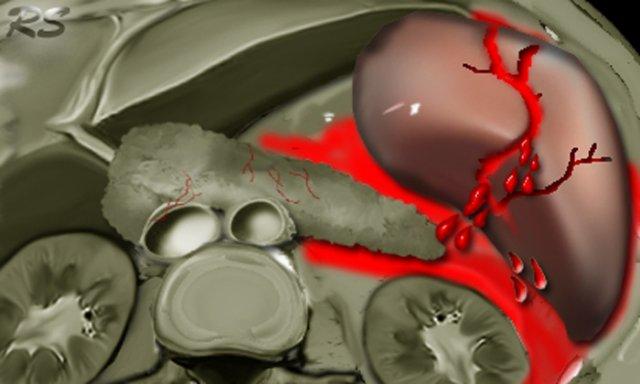

Trước tiên hãy quan sát các hình ảnh bên trái của bệnh nhân bị chấn thương gan.

Mô tả các dấu hiệu hình ảnh.

Sau đó tiếp tục.

Các dấu hiệu bao gồm:

- Mũi tên xanh lá: vùng giảm tỷ trọng hình bầu dục phù hợp với tụ máu

-

Mũi tên vàng: vùng giảm tỷ trọng hình tuyến tính phù hợp với đường rách.

Lưu ý rằng đường rách này đi qua nhánh trái của tĩnh mạch cửa - Mũi tên xanh dương: vùng giảm tỷ trọng mờ, ranh giới không rõ phù hợp với dập gan

- Dịch quanh gan

- Gần như có sự đứt ngang hoàn toàn của gan, nhưng cả hai thùy đều còn ngấm thuốc, cho thấy nguồn cung cấp mạch máu vẫn còn bình thường.